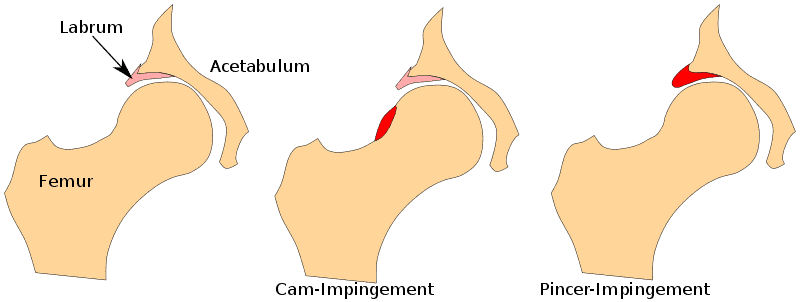

L'impingement femoroacetabolare (FAI), noto anche come impingement dell'anca, si riferisce ad alterazioni morfologiche dell'acetabolo e/o del collo del femore che portano all'impattamento del labbro dell'anca durante il movimento. Si possono distinguere due tipi principali: Quando la testa del femore è troppo grande, si parla di morfologia CAM (più comune negli uomini) e un bordo acetabolare troppo esteso è chiamato morfologia Pincer ed è più comune nelle donne. In un tipo misto, sono presenti sia la morfologia CAM che quella Pincer.